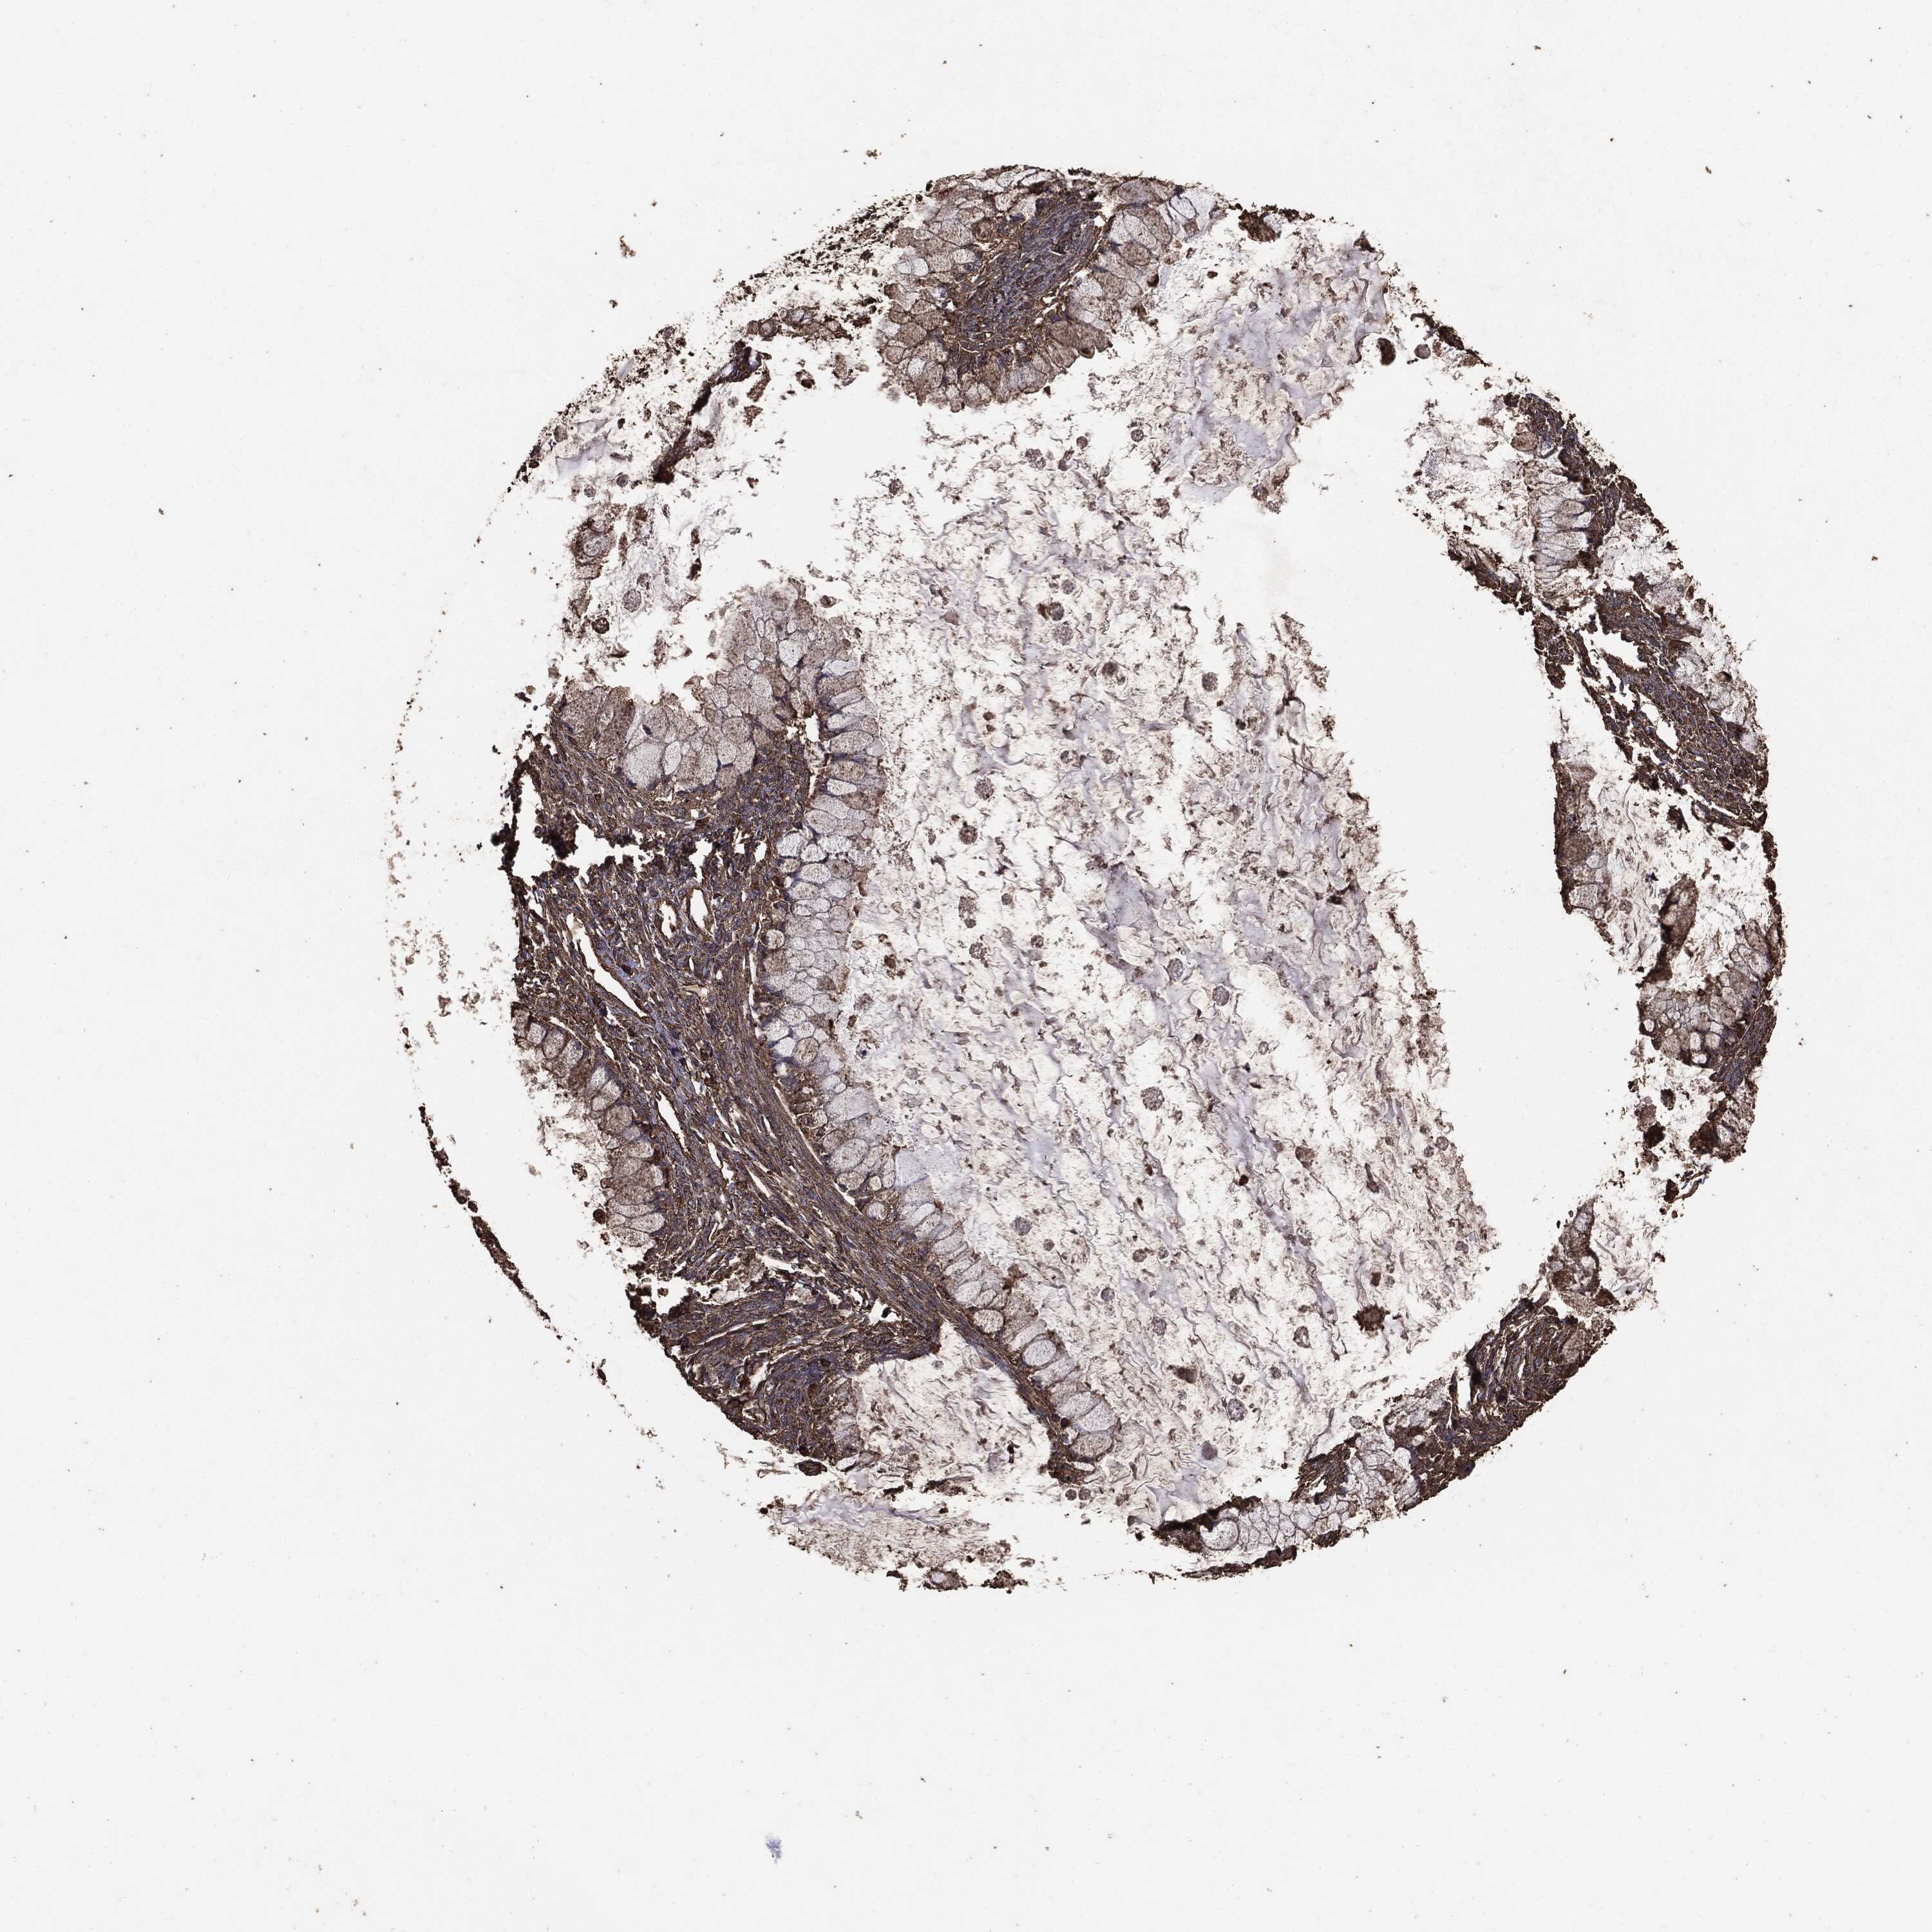

OVARIAN CANCER - Protein expressioni

A mouse-over function shows sample information and annotation data. Click on an image to view it in a full screen mode. Samples can be filtered based on level of antibody staining by selecting one or several of the following categories: high, medium, low and not detected. The assay and annotation is described here.

Note that samples used for immunohistochemistry by the Human Protein Atlas do not correspond to samples in the TCGA dataset.

Antibody stainingi

Antibody staining in the annotated cell types in the current human tissue is reported as not detected, low, medium, or high, based on conventional immunohistochemistry profiling in selected tissues. This score is based on the combination of the staining intensity and fraction of stained cells.

Each image is clickable and will lead to virtual microscopy that enables deeper exploration of all samples and also displays staining intensity scores, fraction scores and subcellular localization as well as patient and tissue information for each sample.

Carcinoma, endometroid